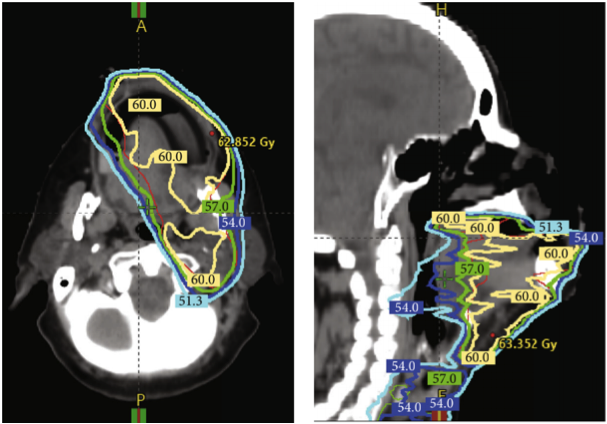

一名63岁绝经后女性,有高血压、高脂血症病史和25包/年的吸烟史,被诊断为口腔鳞状细胞癌病理IVA期(pT1N2bM0)。患者接受了广泛牙槽嵴病变的局部切除术,左颈I-IV区淋巴结清扫术,并用右前臂桡侧游离皮瓣重建;边缘为阴性,没有节外延伸。随后,使用调强放射治疗(IMRT)对图1(a)和1(b)所示区域进行了30次60 Gy剂量的术后放射治疗。

图1. 放射治疗的剂量和口腔的照射区域